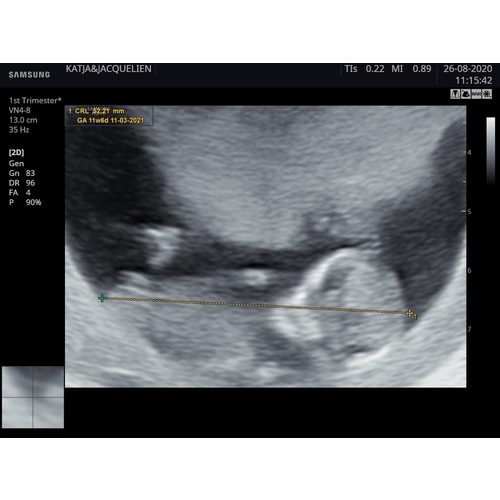

Dit is bij 13 weken, ik dacht zelf een jongen te zien volgens nub. Toen was nog niks tussen de benen te vinden op de echo. Nu bij 15 weken overduidelijk een jongen, dus had het met de nub juist.

Bij ons waren er verschillende antwoorden gegeven, zowel jongen als meisje. Het word een meisje 馃挅 de echo was van 11+5